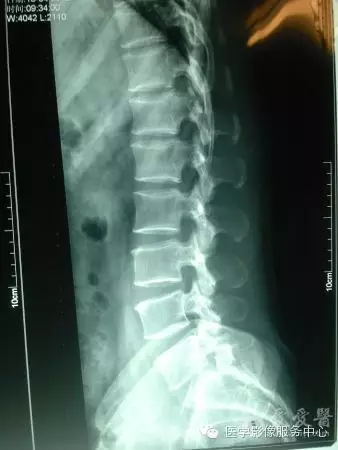

腰椎滑脫分度

椎體滑脫程度分級-Meyerding分級

將下位椎體上緣分為4等分,依據上位椎體對下位椎體向前滑移的程度分為4度:

- Ⅰ度:椎體向前滑移程度不超過椎體中部矢狀徑的1/4。

- Ⅱ度:椎體向前滑移程度超過椎體中部矢狀徑的1/4,但不超過2/4。

Ⅲ度:椎體向前滑移程度超過椎體中部矢狀徑的2/4,但不超過3/4。

V度:椎體向前滑移程度超過椎體中部狀徑的3/4。